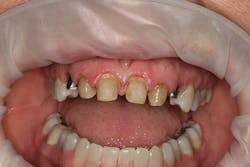

A 32-year-old white female presented for a cosmetic consultation. The patient reported that during her teenage years she had received orthodontic treatment to move her permanent maxillary canines mesially into the spaces that should have been occupied by her congenitally missing lateral incisors. She stated that her dentist, orthodontist, and oral surgeon had decided to place endosseous implants in the canine spaces due to the greater availability of bone in comparison to the bone available in the lateral positions (figure 1). As she grew older, she had become increasingly dissatisfied with the appearance of her smile and was seeking a more updated and esthetic solution (figure 2).

Figure 2